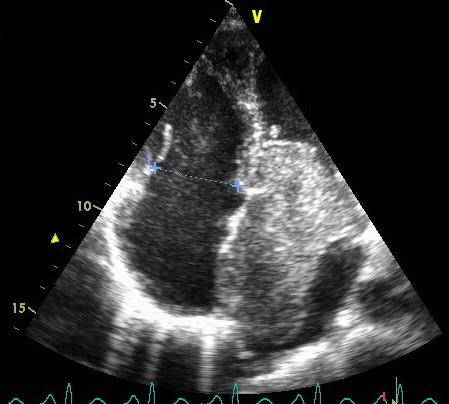

Myxoma is the most common primary tumor of the heart and can arise in any of the cardiac chambers. This paper reports A 50 -year-old woman without medical history and any cardiovascular risk factors was hospitalized for exertional dyspnea and palpitations from three months and signifiant weight loss. Transthoracic echocardiogram showed a giant left atrial myxoma mobile confined to the left atrium in systole, in diastole the tumor was seen prolapsing across the mitral valve into the left ventricle and partially obstructing it and causing severe functional mitral stenosis with a mean gradient of 21,3 mmHg. Severe pulmonary hypertension was confirmed by Doppler PAPs =137 mmHg. The patient was scheduled for cardiac surgery with good outcome.

黏液瘤是最常见的原发性心脏肿瘤,可发生于任何心腔。本文报告一名50岁女性,无病史及任何心血管危险因素,因劳力性呼吸困难、心悸3个月及显著体重减轻入院。经胸超声心动图显示一个巨大的左房黏液瘤,收缩期局限于左房,舒张期可见肿瘤经二尖瓣脱垂入左心室并部分阻塞,导致严重的功能性二尖瓣狭窄,平均压差为21.3 mmHg。多普勒检查证实存在严重肺动脉高压,肺动脉压 = 137 mmHg。该患者接受了心脏手术,预后良好。